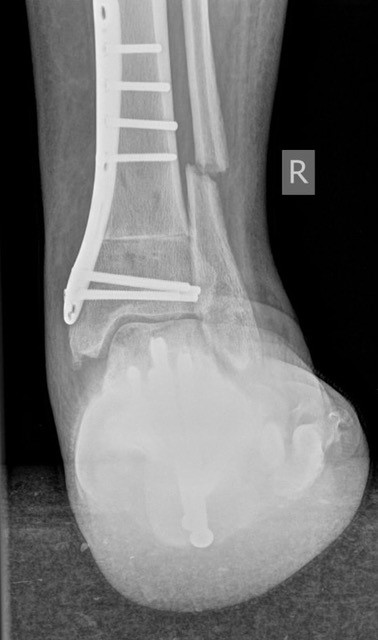

• Fuß belastet dp und seitlich (Abb. 14 und 15)

Typische Merkmale der Standard-Seitaufnahme des Fußes im Stand

• Knöchelgabel ist außen rotiert

• Talus und Calcaneus verlaufen fast parallel

• Sinus tarsi ist einsehbar

• Subtalare Gelenklinie verläuft horizontal und ist breit einsehbar

• Der Abstand Malleolus medialis zum Os naviculare ist verkürzt

• Der Calcaneus erscheint verkürzt

• Der Krümmungsscheitel des Fußes ist erhöht

• Calcaneus pitch ist meist erhöht, der Rückfuß Equinus ist eher selten 12